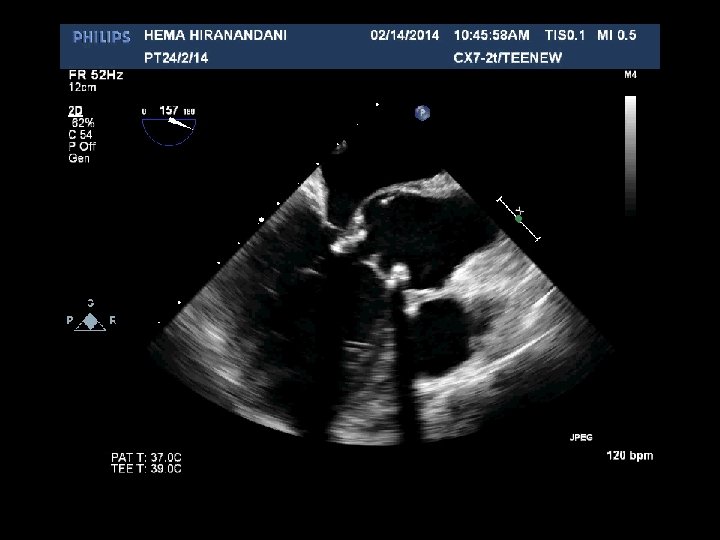

HEMA HIRANANDANI F 57 YRS • • • AVR BIO PROSTHETIC VALVE DEHISCENCE IE MULTIPLE VEGETATIONS ON BIO PRO VALVE AO ROOT ABSCESS SEVERE PARAVALVULAR AR RVSP= 37 mmhg

Hema Hirandani